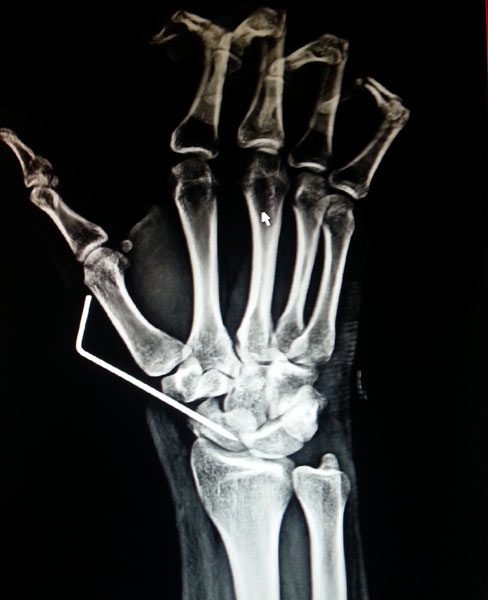

A case of scaphoid non-union

The young, male patient had the fracture of Rt scaphoid/ due to falling on an outstretched hand. The scaphoid fracture was treated, with the plaster cast for 1 ½ month elsewhere. Fracture of Rt Scaphoid was not united. This condition is called, the scaphoid non-union. It was treated with open reduction, and the iliac crest, bone grafting, and K wire stabilization.

Before Surgery